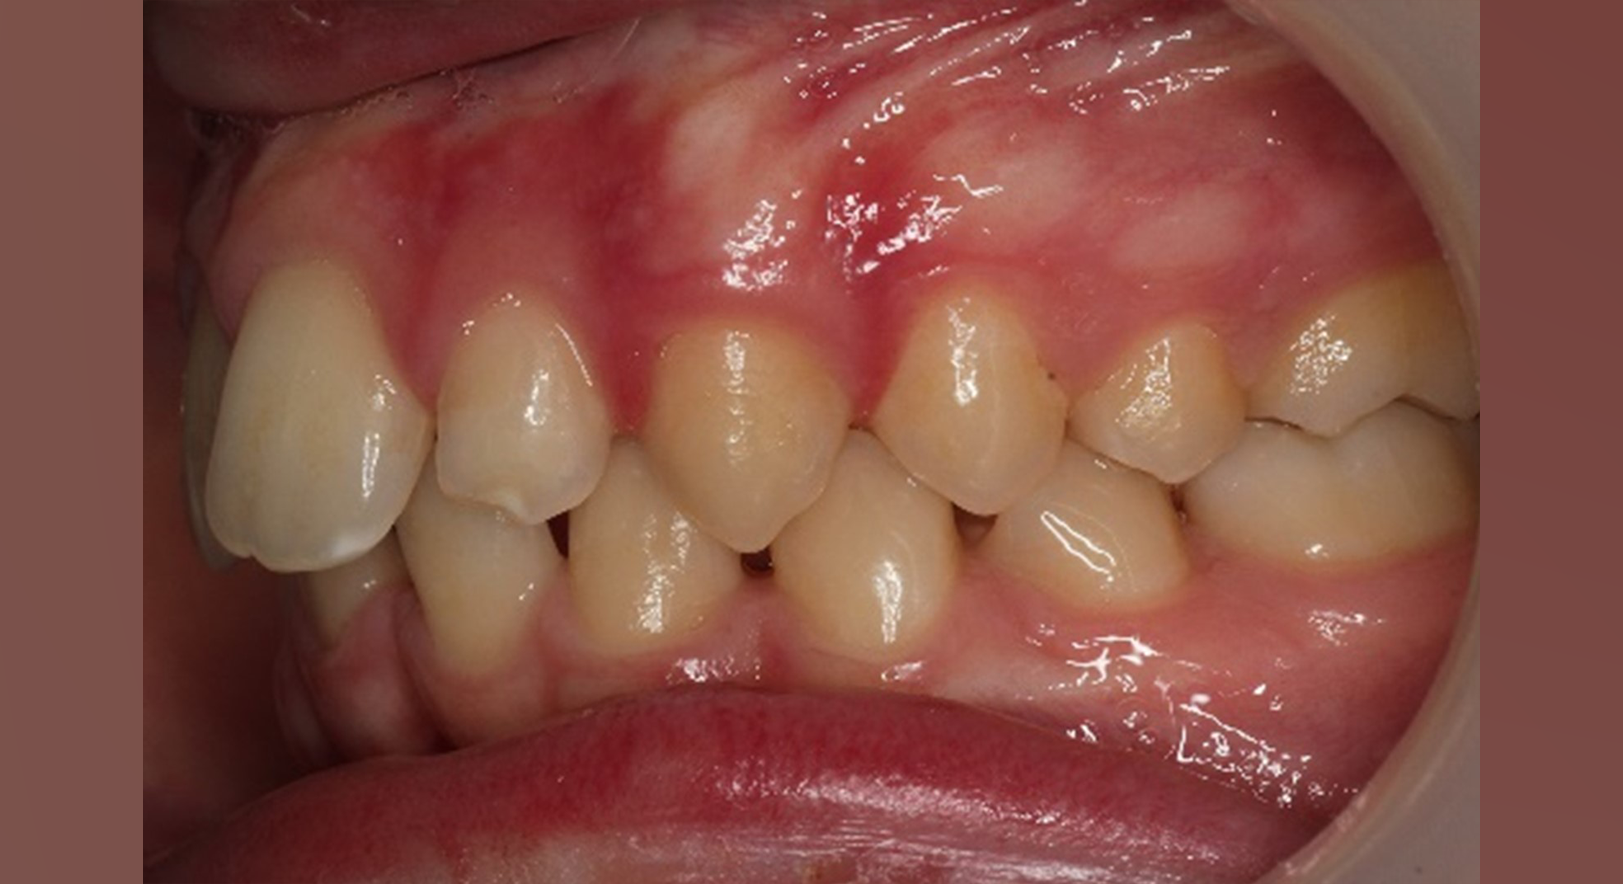

Skeletal Class II due to mandibular retrognathia, proclination of maxillary incisors, narrow arch creating a V-shaped arch, agenesis of 12, 31, 41, hyperdivergent facial pattern, moderate deep bite (2 mm), increased overjet (9 mm), asymmetric canine and molar Class II due to mandibular deviation to the left, maxillary midline deviation related to agenesis of 12, distal rotation of 35 and 45, and pronounced lower curve of Spee.

After 6 months:

Overjet reduced from 9 mm → 4 mm

Clear improvement in labial competence, nasal breathing, and tongue function.